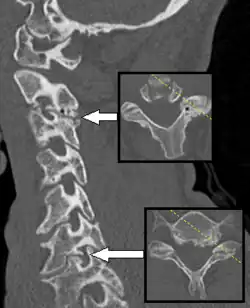

If symptoms do not improve after 4–6 weeks of conservative treatment, or the person is more than 50 years old, further tests are recommended.[3] The American College of Radiology recommends that projectional radiography is the most appropriate initial study in all patients with chronic neck pain.[13] Two additional diagnostic tests that may be of use are magnetic resonance imaging and electrodiagnostic testing. Magnetic resonance imaging (MRI) of the portion of the spine where radiculopathy is suspected may reveal evidence of degenerative change, arthritic disease, or another explanatory lesion responsible for the patient's symptoms. Electrodiagnostic testing, consisting of NCS (nerve conduction study) and EMG (electromyography), is also a powerful diagnostic tool that may show nerve root injury in suspected areas. On nerve conduction studies, the pattern of diminished compound muscle action potential and normal sensory nerve action potential may be seen given that the lesion is proximal to the posterior root ganglion. Needle EMG is the more sensitive portion of the test, and may reveal active denervation in the distribution of the involved nerve root, and neurogenic-appearing voluntary motor units in more chronic radiculopathies. Given the key role of electrodiagnostic testing in the diagnosis of acute and chronic radiculopathies, the American Association of Neuromuscular & Electrodiagnostic Medicine has issued evidence-based practice guidelines, for the diagnosis of both cervical and lumbosacral radiculopathies.[14][15] The American Association of Neuromuscular & Electrodiagnostic Medicine has also participated in the Choosing Wisely Campaign and several of their recommendations relate to what tests are unnecessary for neck and back pain.[16]